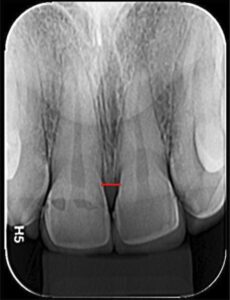

O Exame Radiográfico evidencia Perda Óssea

Exame Radiográfico

O exame Radiográfico é muito importante, deve ser observado o volume e a posição da crista óssea para que se tenha uma melhor condição de previsibilidades, viabilidade e escolha da técnica a ser utilizada. (RX Periapical e Interproximal)